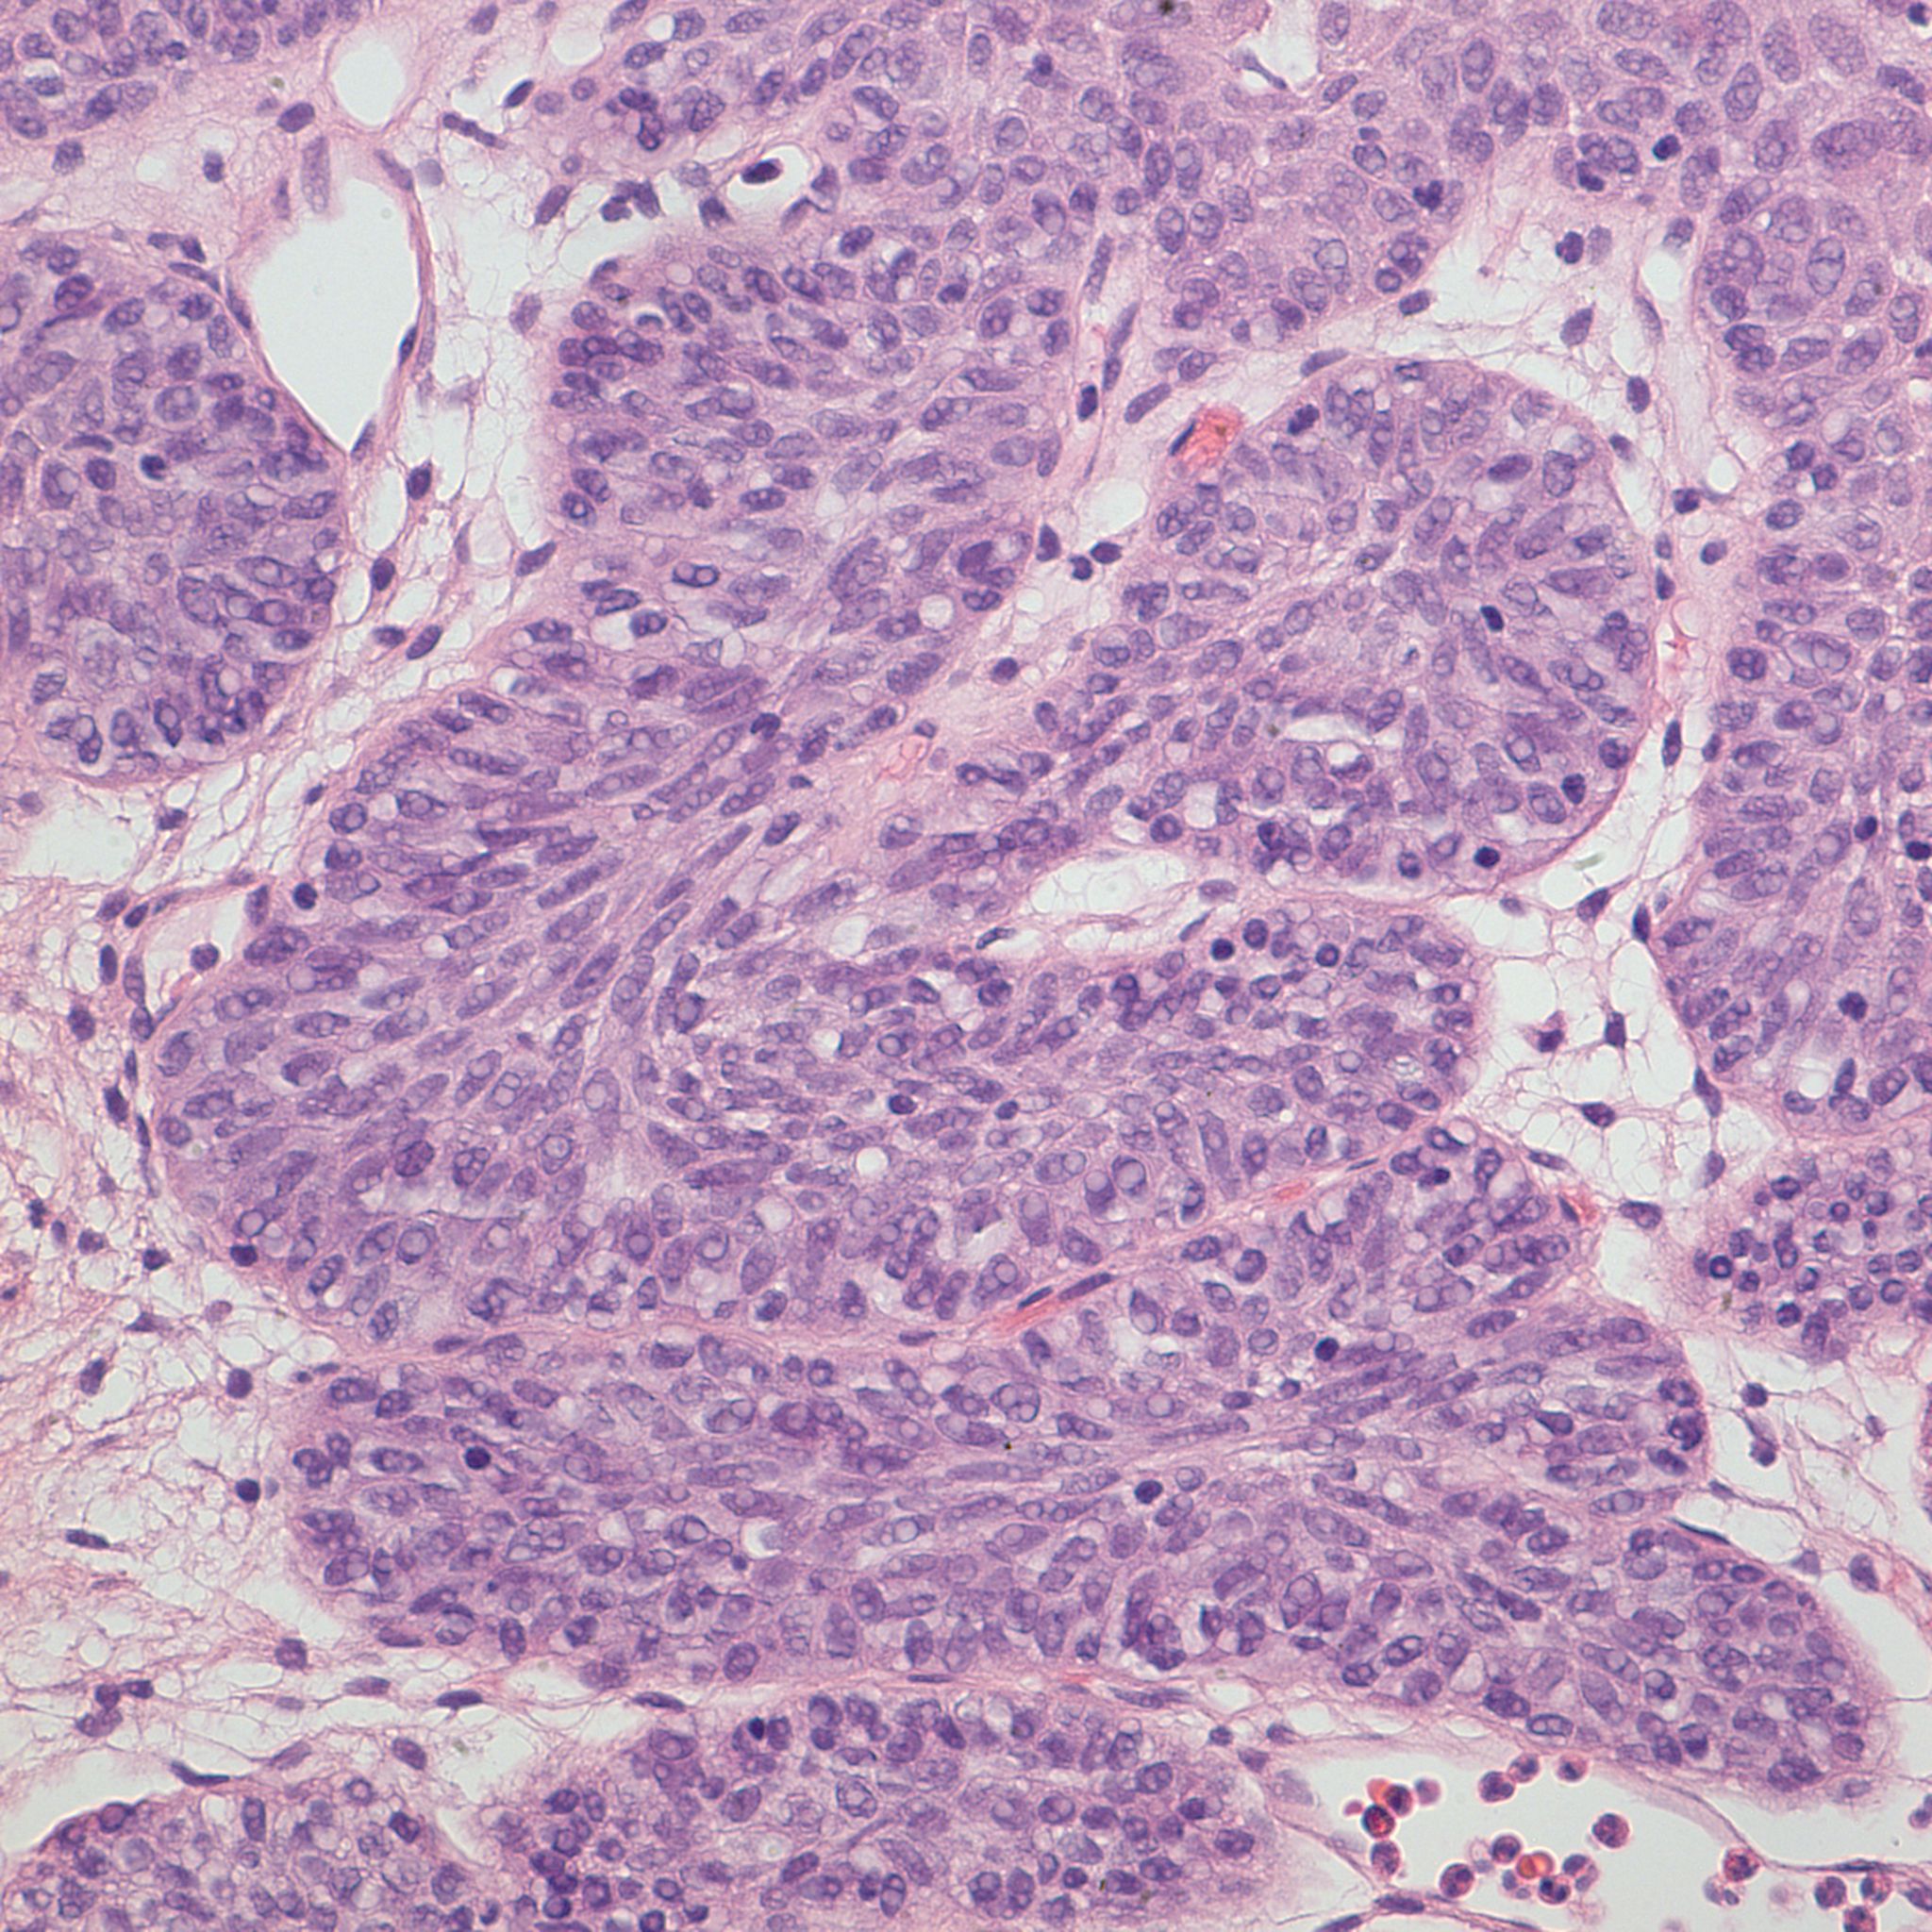

Bladder Papillary Lesions

Case ID: 309

Papilloma

PUNLMP

Low-grade papillary urothelial carcinoma (LG-PUC)

High-grade papillary urothelial carcinoma (HG-PUC)